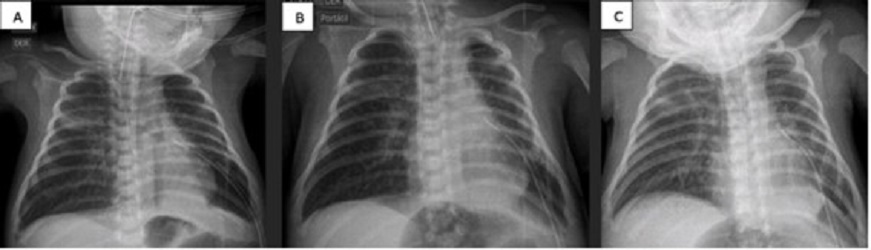

A 9-day-old female baby, born at 32 GW (1224 g), diagnosed with early onset sepsis, respiratory distress syndrome, and pulmonary hypertension. Placed on HFV with FiO2 at 94%. Due to right tension pneumothorax, chest tube placement was also required. Pneumothorax persisted for more than 5 days (labeled when air bubbles continue to drain nito underwater seal device for more than 5 days). ABPP was performed and improvement was noted at 48 hours (no bubbles, radiographic improvement, and decrease in ventilatory parameters). The chest tube was removed on the 19th day of life (Fig. 1).

Figure 1

A) Chest x-ray before pleurodesis. B) Chest x-ray 24 hrs post-pleurodesis. C) Chest x-ray 48 hrs post-pleurodesis. D) Chest x-ray 72 hrs post-pleurodesis.